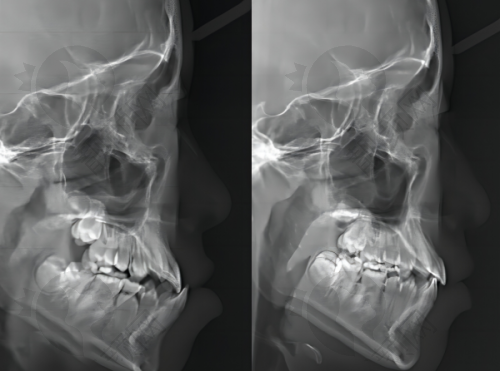

光靠肉眼观察面部外观和牙齿咬合关系还不够正确,这时候就需要借助影像学检查了。常见的影像学检查方法有X光和CT。通过拍摄X光片,医生可以清晰地看到牙齿和颌骨的结构。在X光片上,能够测量下颌骨的角度、长度以及上颌骨和下颌骨之间的位置关系。对于轻度的骨性地包天,X光片可能显示下颌骨的角度只是稍微有点异常,上颌骨和下颌骨之间的距离变化不是较大。

而中度和重度的骨性地包天,在X光片上的表现就会更明显。下颌骨的角度会明显增大,上颌骨可能会出现发育不足的迹象,上下颌骨之间的位置关系重度失调。CT检查则更加严谨,它可以提供三维的图像,让医生从不同的角度观察颌骨的形态和结构。通过CT,医生能够更正确地判断骨性地包天的重度程度,为制定治疗方案提供更详细的信息。

比如说,在制定手术治疗方案的时候,医生就可以根据CT图像来严谨地规划手术的部位和范围,确保手术能够达到至佳的治疗成效。而且,通过多次的影像学检查,还可以观察患者在治疗过程中颌骨的变化情况,及时调整治疗方案。